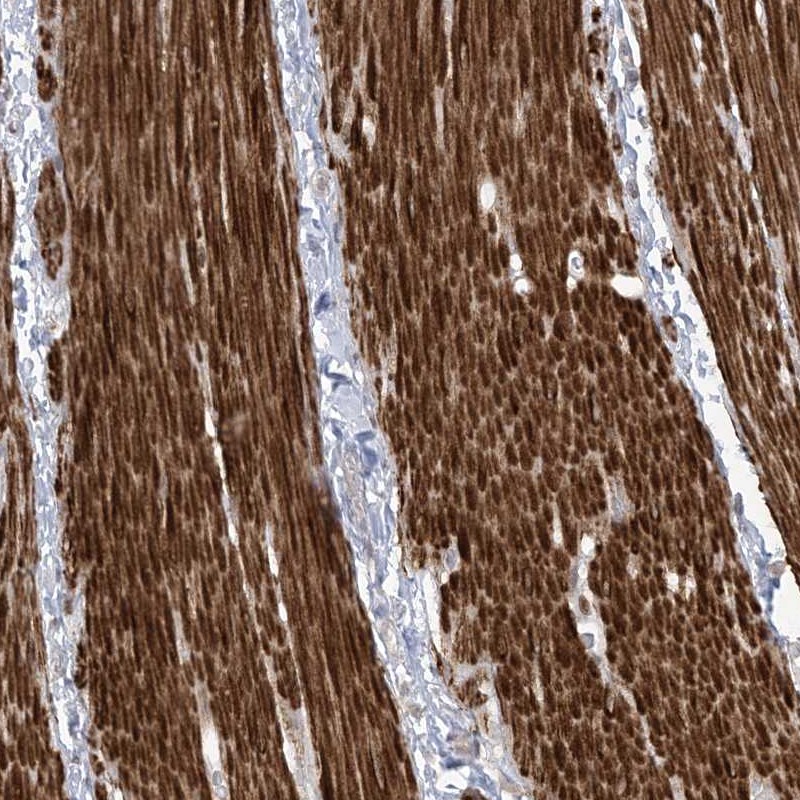

Immunohistochemical staining of human smooth muscle shows strong cytoplasmic positivity in smooth muscle cells.